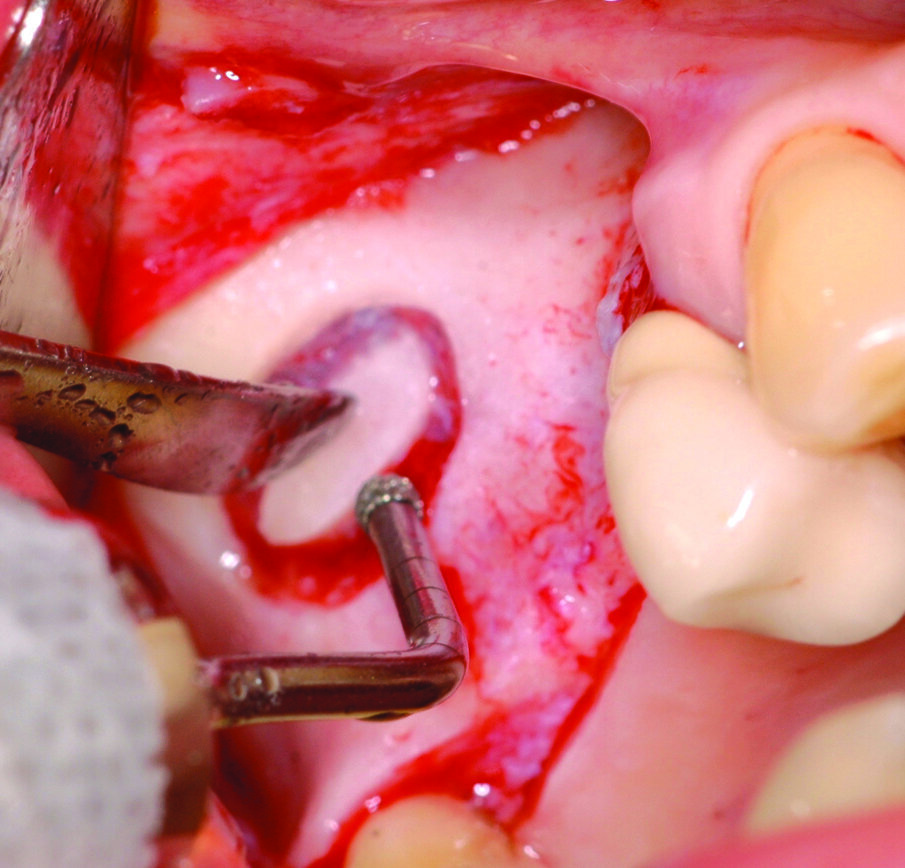

Di seguito viene valutata l’anatomia del seno mascellare, in particolare analizzando l’angolo tra la parete mediale e la parete laterale del seno, che ne determina l’ampiezza3. Vista l’assenza di setti e data la buona ampiezza del seno mascellare viene scelto un approccio per via laterale, in grado anche di consentire un miglior controllo dei volumi ossei innestati, considerando che gli impianti da inserire sono due. Si procede, quindi, con l’allestimento di un lembo a tutto spessore con tagli di scarico sia mesiale che distale (Figg. 2, 3) e a un’antrostomia per riflessione con bisturi piezoelettrico (Surgybone, Silfradent, Italia) (Fig. 4), che permette un miglior controllo dell’osteotomia4-5, riducendo il rischio di perforazione della membrana di Schneider.

Una volta eseguito il disegno dell’antrostomia (Fig. 5), si procede al sollevamento della membrana con tecnica manuale (Figg. 6, 7) e all’iniziale inserimento di biomateriale granulare 0,5-1 mm (AlphaBio’s Graft, Alpha-Bio Tec, Israele). La corticale viene lasciata integra e aderente alla mucosa schneideriana in modo da diventare il futuro pavimento dell’antro (Fig. 8), anche per supportare il collasso della membrana durante il periodo di guarigione. A protezione della stessa è inserita una spugnetta di collagene equino (Condress, Smith&Nephew, UK). Contestualmente si procede con l’inserimento di due impianti autofilettanti SPI 3.75 x 13 mm (Alpha-Bio Tec, Israele) (Figg. 9, 10) e, al termine, viene ultimato il riempimento con biomateriale (Fig. 11). L’antrostomia viene poi coperta con una membrana riassorbibile 15 x 20 (AlphaBio’s Graft, Alpha-Bio Tec, Israele) e il lembo viene passivato e suturato con due linee di sutura 5-0: una a materassaio orizzontale e l’altra con punti staccati (Vicryl, Ethicon, USA) (Fig. 12). La paziente viene dimessa con la seguente terapia farmacologica: amoxicillina cpr 1 gr (1 cpr ogni 12h per 6 giorni), Prednisone cpr 25 mg (2 cpr per due giorni a scalare) per il controllo dell’edema post-operatorio e sciacqui con clorexidina 0.2% dal giorno successivo (1 sciacquo al giorno per 15 gg). Le suture sono rimosse a 15 giorni e la paziente è inserita in un programma di recall a cinque settimane per gestire eventuali complicanze durante la maturazione dell’innesto. Viene eseguito il secondo tempo chirurgico dopo 6 mesi e, verificata l’avvenuta osteointegrazione degli impianti, vengono rilevate le impronte e il caso è finalizzato con due corone unite in metallo ceramica (Figg. 13-15). Al termine della riabilitazione, visto il buon mantenimento igienico, la paziente viene inserita in un programma di follow-up a sei mesi (Figg. 16, 17).

Fig. 9_Fasi dell’osteotomia implantare.